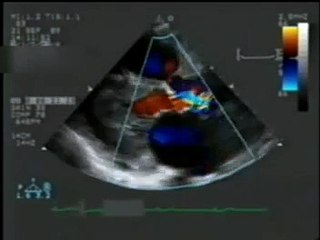

Mitral Regurgitation II (Revisited) - Color Doppler Echocardiogram - Dog

Duration: 00:15